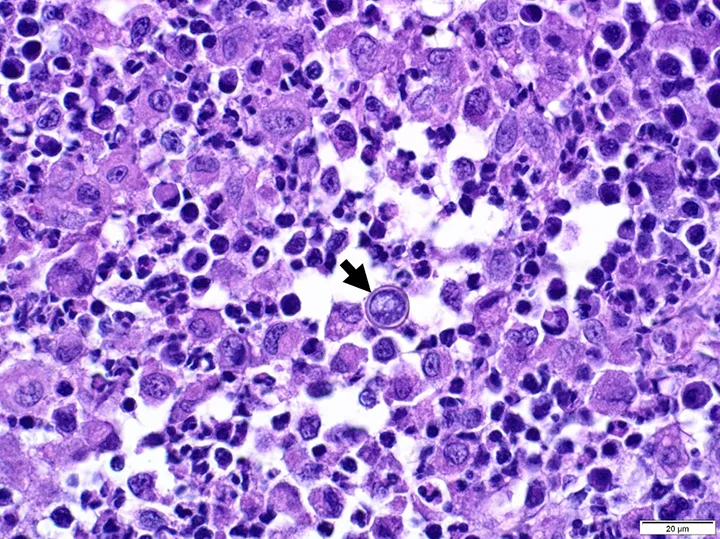

Histopathology showing multifocal-coalescing pyogranulomatous dermatitis and panniculitis and intralesional fungal yeast (arrow). Hematoxylin and eosin stain, 60× magnification. Image courtesy of Dominique Wiener, Dr.med.vet, PhD, DECVP

Ulcerated lesions on the digit after hair was clipped

Hercules was anesthetized for lymphangiogram, surgical biopsies of the dorsal tarsal and digital skin and subcutaneous tissues, and pelvic limb CT (to assess for subtle bony lesions and vascular malformation). Lymphangiogram was normal. Tissue from the digit was submitted for aerobic and anaerobic culture for Nocardia spp and Actinomyces spp growth; one colony of Staphylococcus epidermidis (likely a contaminant) was present. Histopathology of the digit showed severe, regionally extensive, chronic pyogranulomatous panniculitis with rare intralesional yeast most consistent with Blastomyces spp (Figure 4). Mild, diffuse, chronic perivascular lymphoplasmacytic panniculitis of the dorsal tarsus was also noted, likely secondary to Blastomyces spp infection.